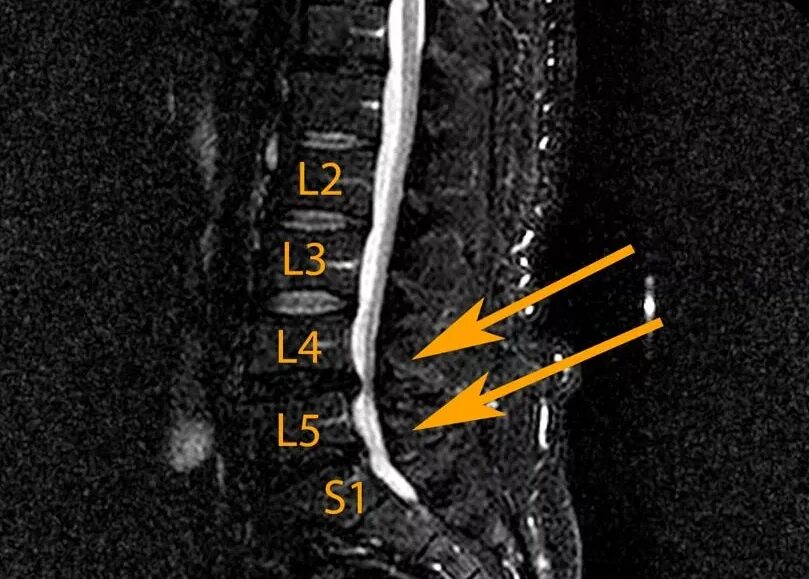

Протрузия диска l2 l3